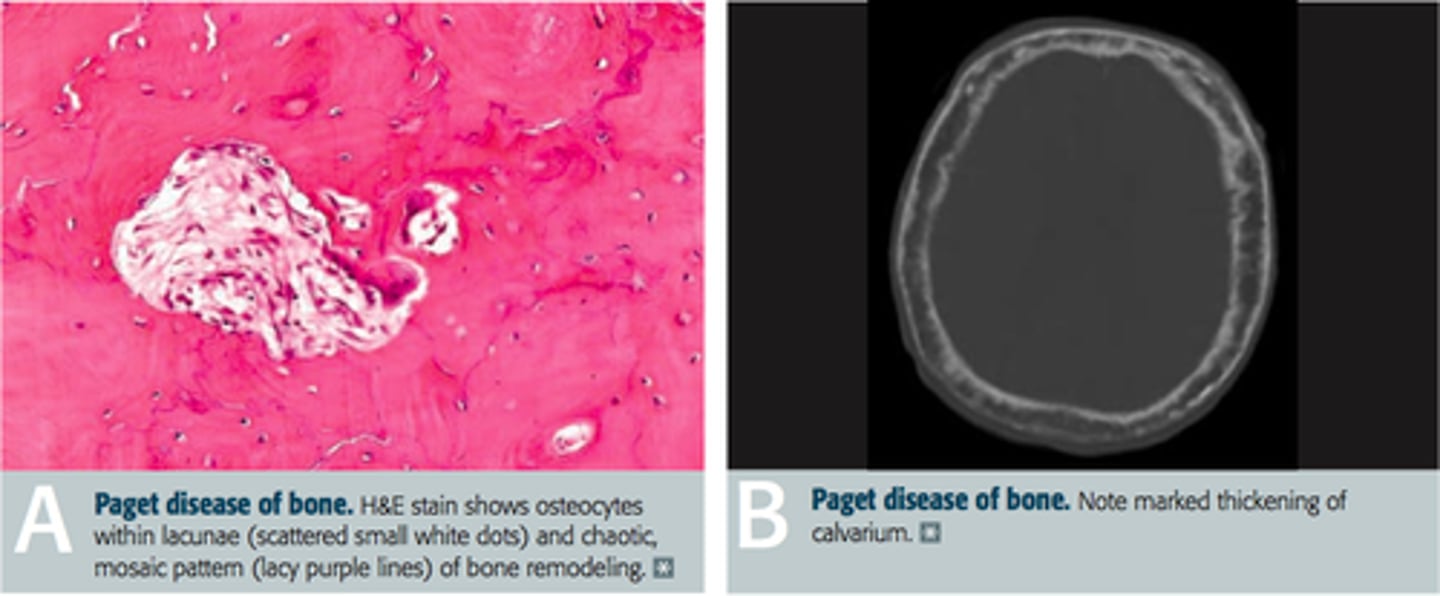

Bone pain, bone enlargement (hat size or hearing loss), arthritis

Paget disease of bone (Increased osteoclastic, then osteoblastic activity)

Osteosarcoma or heart failure